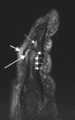

Magnetic resonance image of the سبابة in psoriatic arthritis (mutilans form). Shown is a T2 weighted fat suppressed sagittal image. Focal increased signal (probable erosion) is seen at the base of the middle سلامى (تشريح) (long thin arrow). There is synovitis at the proximal interphalangeal joint (long thick arrow) plus increased signal in the overlying soft tissues indicating استسقاء (طب) (short thick arrow). There is also diffuse bone oedema (short thin arrows) involving the head of the proximal phalanx and extending distally down the shaft.